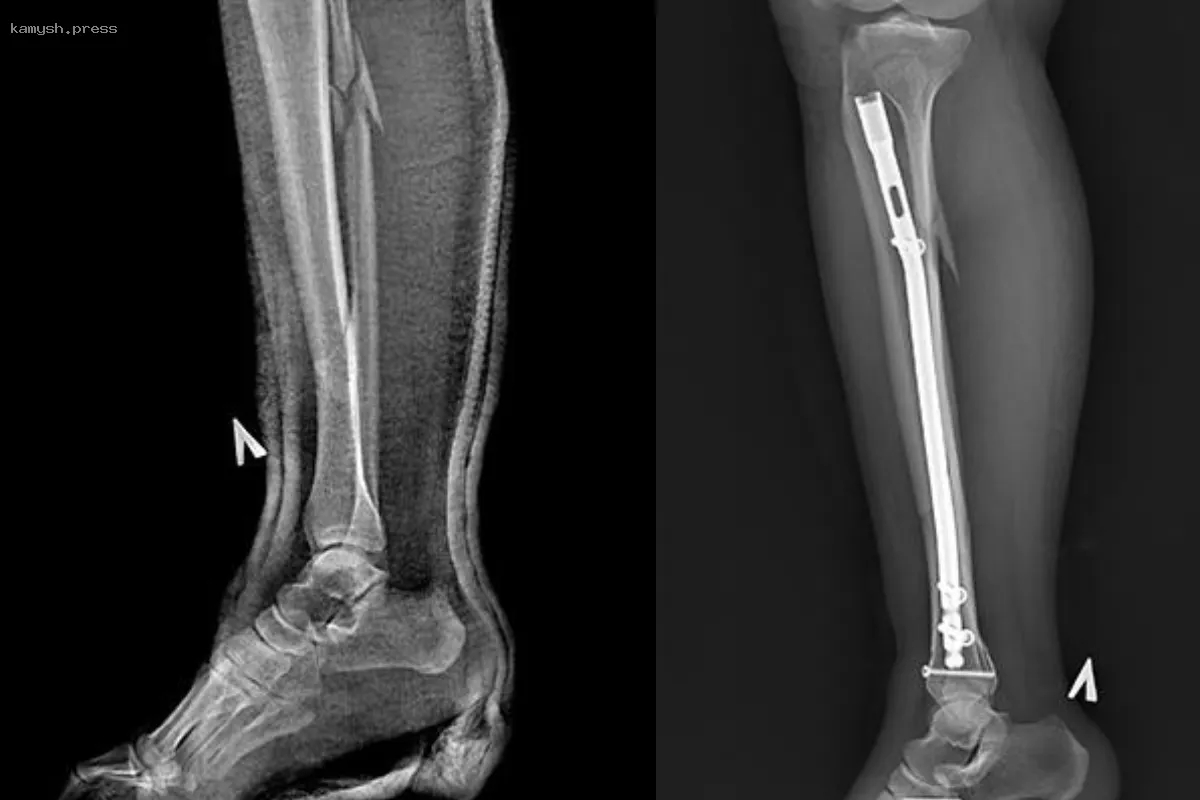

В отделении травматологии Пушкинской клинической больницы имени профессора Розанова В.Н. прооперировали 30-летнюю женщину, неудачно прогулявшуюся по улице на высоких шпильках: она сломала ногу в трех местах: оскольчатый перелом костей голени, большой берцовой и малой берцовой костей.

Женщине ввели спинальную анестезию и провели остеосинтез для закрепления обломков кости. Такой метод, объясняет травматолог-ортопед Александр Первухин, исключает вероятность вторичного смещения и последствий вроде тромбоза, остеопороза, артроза, а также не требует ношение гипса.

Женщине установили металлоконструкции, которые снимут через год, а пока она будет пользоваться костылями. Гипс в ее случае использовать не стали.

Пациентка теперь будет пользоваться костылями, на поврежденную ногу можно наступать, через год ей снимут все металлоконструкции, а до этого будут наблюдать за состоянием.